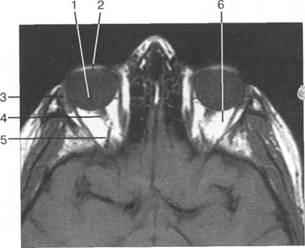

opticus).

(a. ophtalmica).

(v. ophtalmica).

HU), каплив 121h711b ают контрастный препарат. Толщина хнюю прямую мышцу видно плохо, обычно ее изображение слив 121h711b ается с изображением мыш­

На КТ-изображениях глазное яблоко имеет шаровидную структуру, четко выраженную обо­лочку, внутри его определяется хрусталик эллиптической формы размером 4x9 мм, плотностью

HU.

HU

четлив 121h711b о дифференцировать зрительный нерв и глазодвигательные мышцы (рис. 2.16, 2.17).

нижняя косая мышца отчетлив 121h711b о